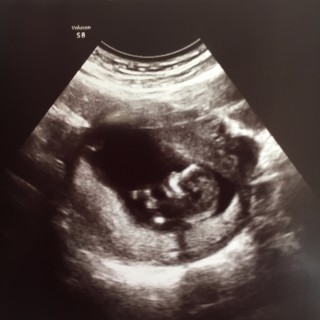

12w3dのエコーです。約2週間振りの診察。 4cmから6cmになっていました。成長ゆっくりかなと思いましたが先生からは順調で標準だよと言われ安心しました。 不妊治療でやっと授かった我が子です。 本当に元気に育ってくれてありがとう! このまま大きく元気に育ちますように!

CRL5.78㎝

手足バタつかせていて元気な子でした